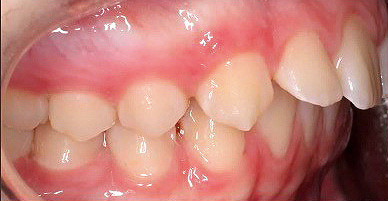

Klinisches Fallbeispiel 1 (Abb. 1a–u)

Neunjähriger Patient mit deutlich vergrößertem Overjet aufgrund eines Distalbisses in Kombination mit einer Protrusion der Oberkieferfront. Habits bzw. myofunktionelle Aspekte wurden adressiert. Die Behandlung erfolgte mit einem Invisalign-Schienensatz (56 Aligner) mit Precsion Wings im Rahmen einer Frühbehandlung zur Prophylaxe eines Frontzahntraumas.